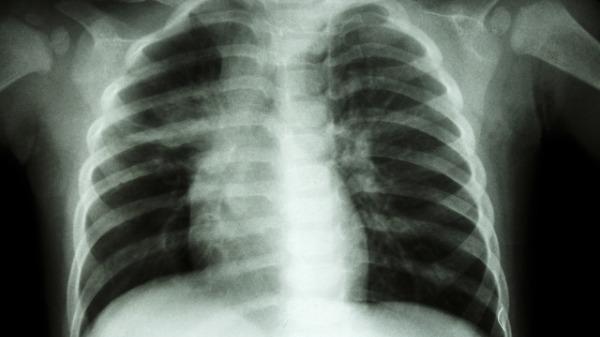

近日,湖南。一男子称自己一直咳嗽,到医院检查才发现双肺感染,断了3根肋骨。男子称,刚开始是有些发烧但是不严重,后来断断续续咳嗽一周左右开始加重,咳得肚子痛、胸痛。在诊所打吊针无效果后男子来到医院检查拍片,结果显示自己核酸没有阳,但是肺部感染,断了3根肋骨,他呼吁大家一定要重视咳嗽。